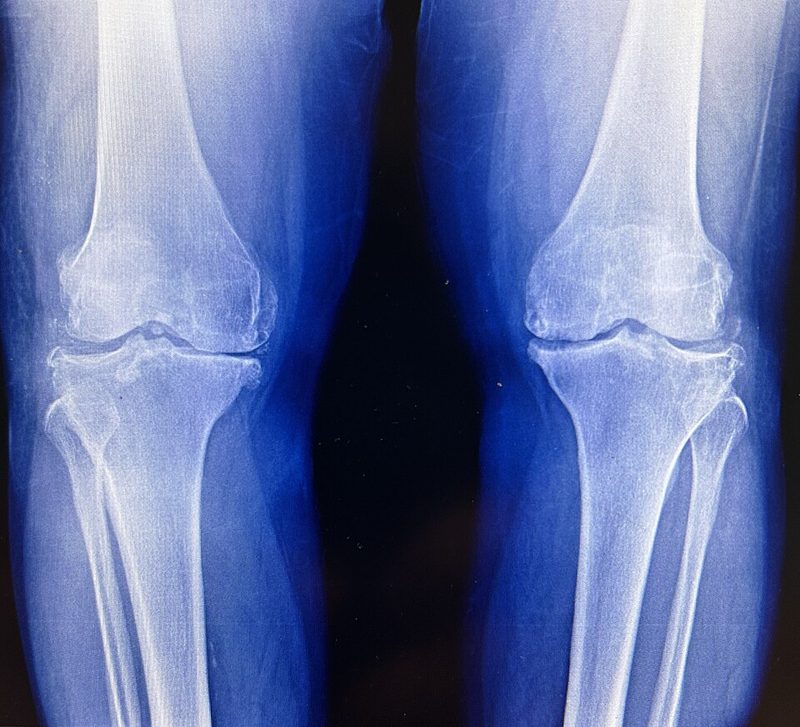

Osteoartritis de rodilla — radiografia mostrando desgaste articular

Wikimedia Commons / CC BY-SA 4.0

La causa más comun despues de los 45 anos es la osteoartritis. Las rodillas soportan todo el peso del cuerpo y son las articulaciones que más se desgastan. Sientes: crujidos al subir/bajar escaleras, rigidez al levantarte, dolor despues de estar sentado mucho tiempo.